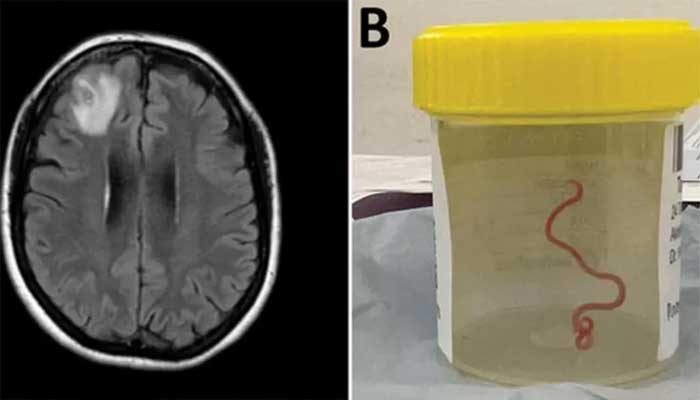

নারীর মস্তিষ্কে মিলল ৮ সেন্টিমিটার জ্যান্ত কৃমি